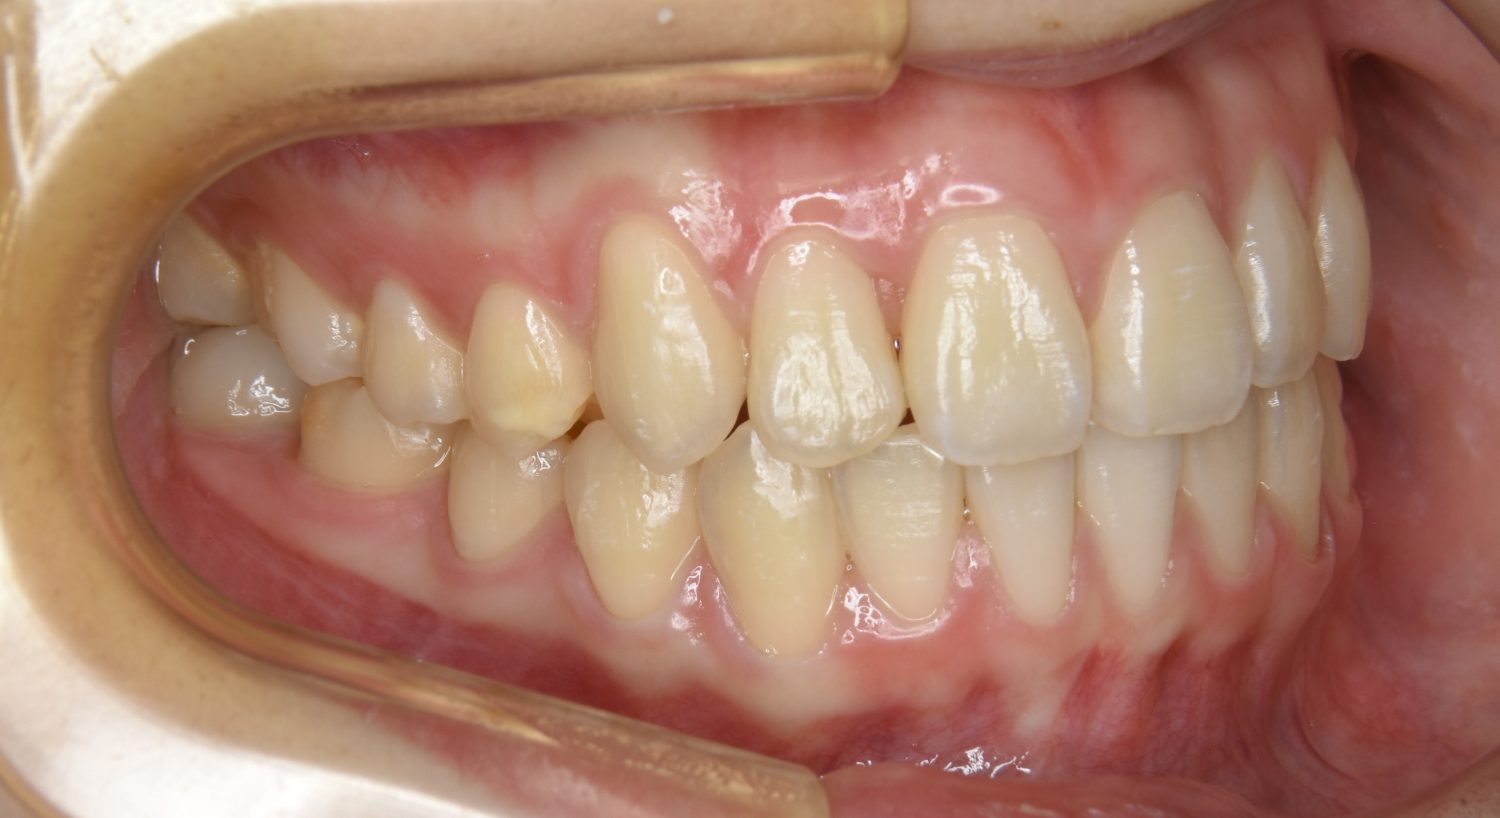

叢生の症例紹介②

Before

After

主訴

歯の凸凹を治したい。

治療内容

アライナー(インビザライン)にて非抜歯で治療を行いました。

治療費

1,150,000 円(税込)

治療期間

26ヶ月

通院回数

14回

想定されたリスク

※歯根吸収、歯肉退縮、歯髄壊死、顎関節症状

※アライナー(インビザライン)は日本の薬機法未承認の矯正装置であり、医薬品副作用被害救済制度の対象外となる場合があります。

丸山和宏先生

ピーススマイル矯正歯科

上下前歯部に叢生(凸凹)が認められる状態でした。歯列の遠心移動を行うことで機能面および審美面が改善されました。